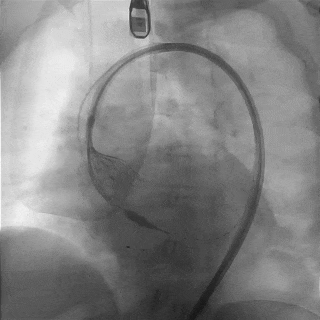

脱钩后造影

瓣膜位置可,无瓣周漏

外周造影检查,血管无损伤